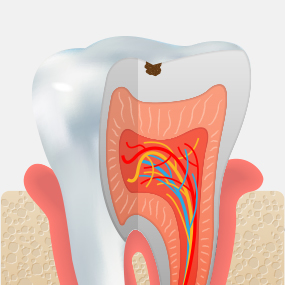

Stages of Dental Caries and Treatment Methods

• Enamel Caries

Decay limited to the enamel, the outer layer of the tooth, with little or no pain.

Resin Restoration

• Dentin Caries

Decay has progressed into the dentin beneath the enamel, and sensitivity may occur when eating hot or cold foods.

Inlay

• Pulpitis

Inflammation has progressed to the dental pulp, causing severe pain that may become difficult to tolerate.

Root Canal Treatment + Crown

• Pulp Necrosis

The tissue inside the tooth has become necrotic, and bone around the root is gradually lost due to infection.

Extraction + Implant